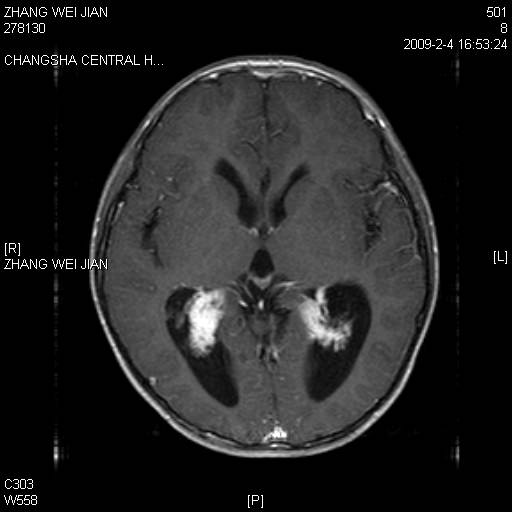

以下是引用guanaishengming在2009-2-6 22:51:00的发言:[br]脉络丛乳头状瘤

以下是引用随光逐影在2009-2-7 8:30:00的发言:[br]考虑双侧脑室脉络丛乳头状瘤并脑积水。

以下是引用同在2009-2-7 15:13:00的发言:[br]脉络丛乳头状瘤并脑积水。